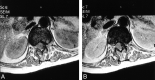

Axial T1-weighted images demonstrate the intramedullary position of the tumor, which occupies nearly the entire spinal canal. A, Nonenhanced image. B, Gadolinium-enhanced image shows mild homogeneous enhancement in the lesion